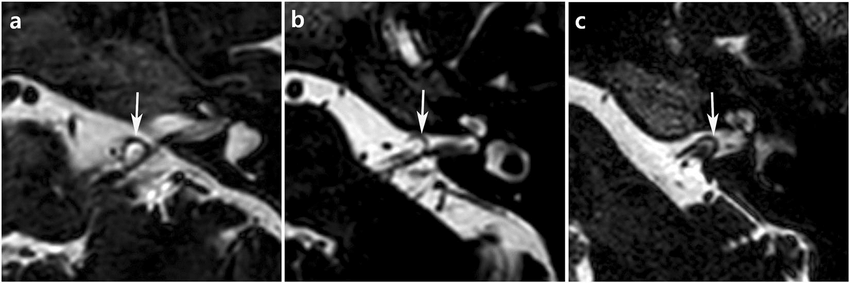

AICA vasküler halkasının anatomik lokasyonuna göre sınıflandırılması nasıldır?

Tip I: Serebellopontin açı seviyesindeki vasküler halka.

Tip II: İç işitsel kanalın proksimalindeki vasküler halka kanalın %50'sinden daha azına kadar uzanır.

Tip III: İç işitsel kanalın distalindeki vasküler halka kanalın %50'sinden fazlasına uzanır.

Serebellopontin açısındaki nörovasküler yapılar 3D FIESTA / CISS MRI dizisinde açıkça tasvir edilmiştir. TOF MR anjiyogramı, arteriyel anatominin mükemmel bir şekilde görüntülenmesini sağladığı için serebellopontin açısındaki bu vasküler döngünün seyrini incelemek için kullanılabilir. Bu diziler döngü tiplerinin sınıflandırılmasına yardımcı olur. Ayrıca ileri FMRI çalışmalarında temas halindeki baskınının bir elektriksel potansiyel değişimine rol oynayıp oynamadığı tespit edilebilir. Sıklıkla diğer asıl tinnitus nedenleri ile karışması nedeniyle diğer nedenlerde detaylıca görüntülenerek asıl tinnitusun kaynağına ulaşılabilir.{C}{C}